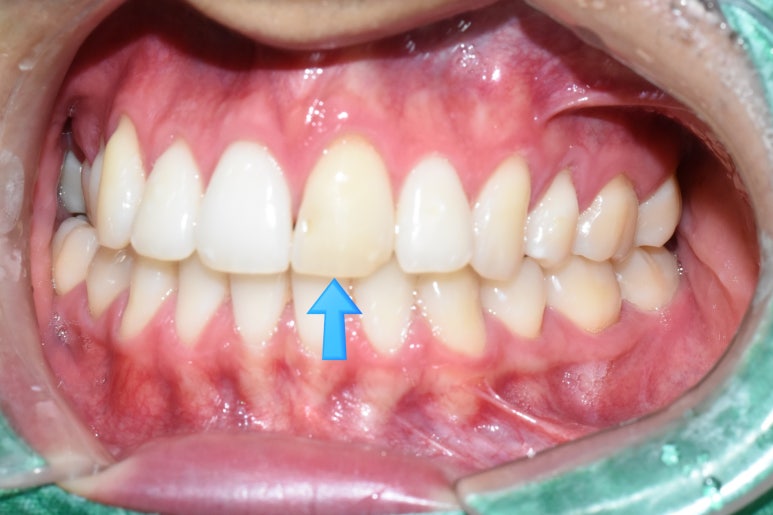

교정을 하신 분들도 많다보니 그 크라운을 해야하는 앞니에

유지장치가 붙어있는 분들도 많으세요.

이런 경우에는 치아 하나의 앞뒤 좌우를 다 깎아서 씌우는

크라운말고

치아를 최소한으로만 삭제하는 최소삭제 라미네이트를 생각해볼 수 있는데요

따라서 이러한 경우에는

뒤에 유지장치를 건드리지 않는 라미네이트를 하여

치아의 변색을 가릴 수 있는 방법을 한가지 옵션으로 생각해 볼 수 있습니다.

위의 사진에서 철사보이시죠?

화살표된 두개 앞니 치아 치료